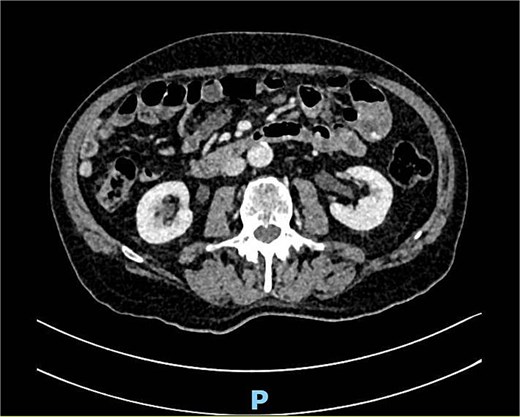

A performed CT scan showed a suspicious process in the left hemiabdomen with the involvement of the small bowel and its mesentery (Fig. 7), as well as enlarged lymph nodes. Therefore a radiological suspicion of malignancy was postulated. Adding to that a mechanical small bowel obstruction was seen in the CT scan due to the described mass.

An antibiotic therapy with piperacillin/tazobactam was empirically initiated as well as a conservative therapy of small bowel obstruction with oral intake of Telebrix®. We also scheduled further investigations ruling out a malignancy. The performed magnetic resonance imaging (MRI) of the abdomen then showed a jejunal diverticulitis (Fig. 8). During the hospital stay we observed a significant decrease of the inflammatory markers, a return of bowel movement with established stool passing as well as a pain-free patient. The antibiotic therapy was discontinued on the day of dismissal, on day 7.

MRI showing multiple jejunal diverticula on the mesenteric side.